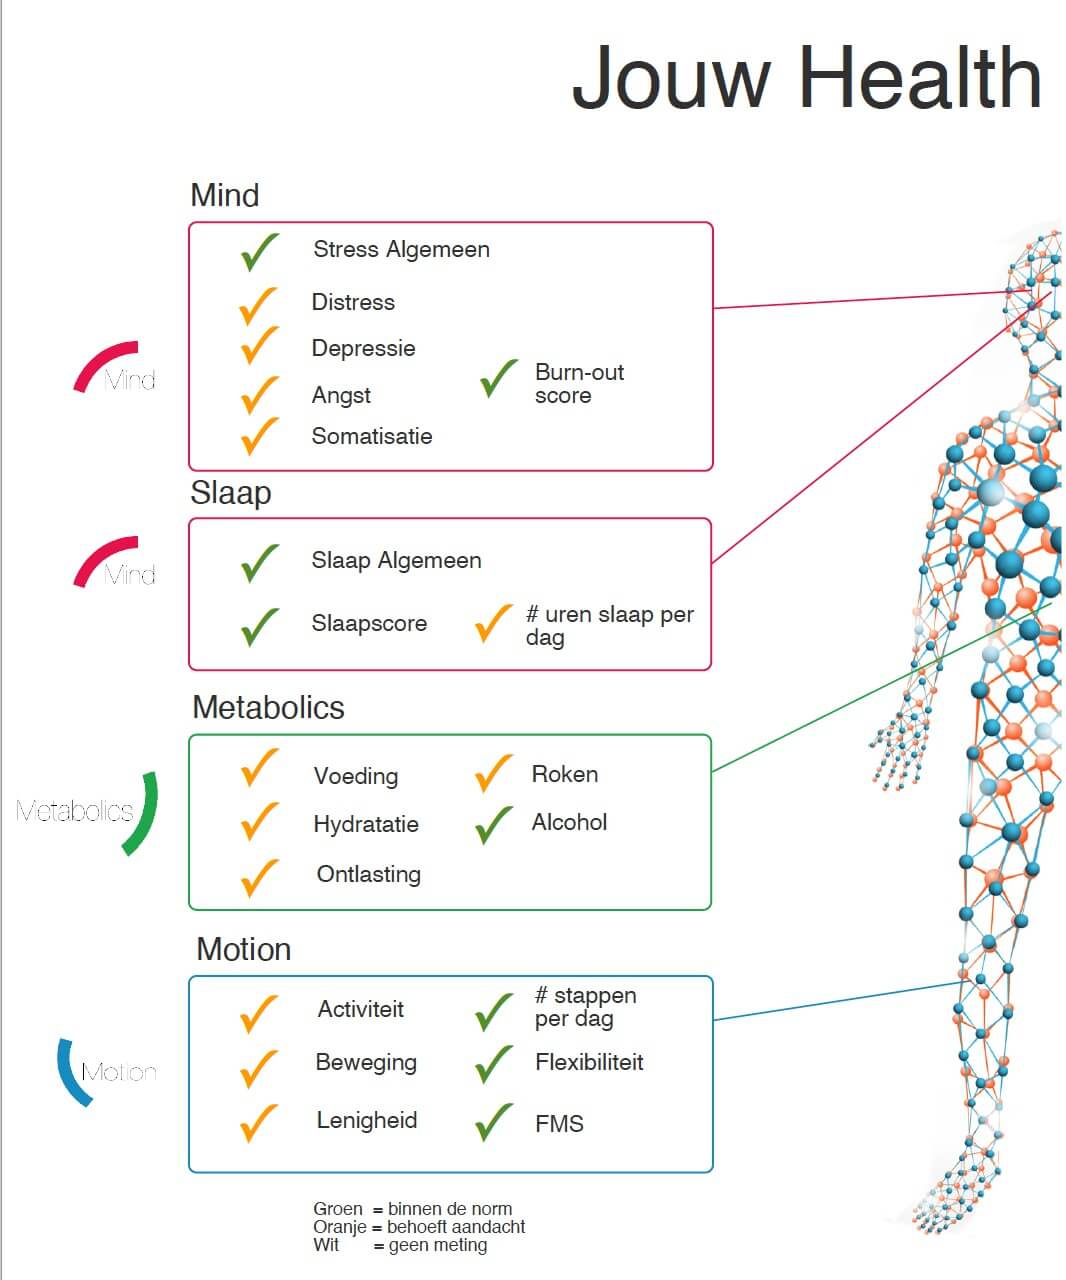

- Biometrie onderzoek: buikomvang, bloeddruk, visceraal vet, gewicht, lengte, BMI, spier%, vet%

- Biomarkers (oa nierfunctie, glucose, ontstekingsparameter, cholesterolprofiel)

- Hartfilmpje (ECG)

- Uitgebreider bloedonderzoek: bloedbeeld en orgaanfuncties (lever, nier, schildklier, pancreas), vitamine D, vitamine B12

- Gehoortest

- Longfunctietest

- Metingen (o.a. bloeddruk, pols, vetpercentage, spiermassa, visceraal vet)

- Bloedonderzoek (o.a. nierfunctie, ontstekingsparameters, glucose, cholesterolprofiel)